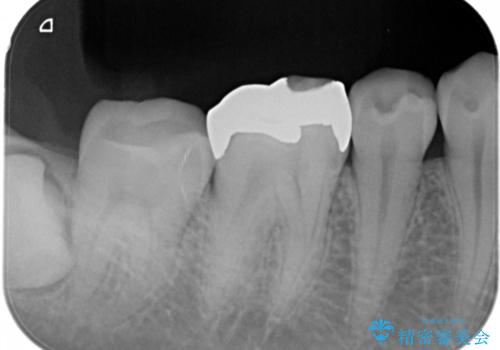

適合不良の補綴物は二次的な虫歯発生のリスクが高まります。

自費診療で用いられる材料は保険適応の材料に比べて、より精密で適合の良い被せ物作ることができるため、長期的な虫歯のリスクを大幅に減らすことが可能です。